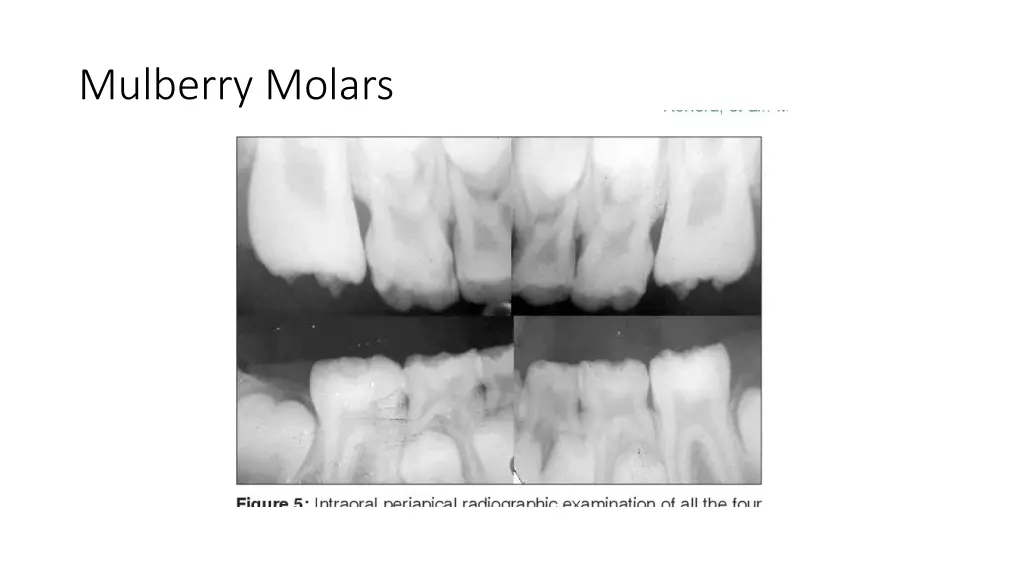

True Anodontia, Partial True Anodontia, Partial False Anodontia, Mesiodens/Supernumerary, Microdontia, Marcrodontia, Gemination/Right Fusion/Left, Peg-Lateral, Fusion Two Roots/Two Crowns, Dens in dente, Dilaceration, Concresences, Taurodontia, Hypercementosis, Amelogenesis Imperfecta, Dentinogenesis Imperfecta, Hutchinson Incisors, Mulberry Molars, Mental Foramens - Radiolucent.